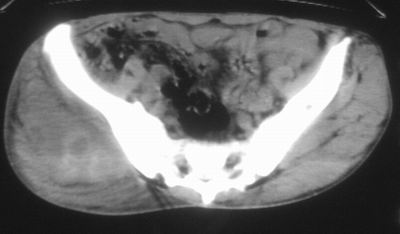

标题: CT16837:M63Y,右臀部巨大软组织包块 [打印本页]

患者,男,63岁,自诉3个月前发现右臀部包块,触及疼痛,治疗后缩小。前天突然增大。无高热病史。

考虑-----右臀大肌,臀中肌---感染性病变可能性大。

恶性软组织肿瘤可能性不大

病灶内部可见出血,首先考虑急性出血性病变.血肿?

给个骨窗,判断一下肿块是否与髂骨有关,肿块内出血是肯定的,至于是感染形成的脓肿还是起源于肌肉或纤维组织的肉瘤则难以确定,不过从影像上看,包膜完整,且环形增厚,病灶下部见斑片状底密度坏死,个人倾向感染可能性大

肌间隙明显混浊,三个月前治疗有缩小,支持考虑臀大肌下脓肿伴出血,肿瘤如果出现瘤内出血的话瘤外边界应该较清楚,现在表现为一种恶性征像,但骨质无明显异常,且臀小肌边界清楚,不符合恶性表现.